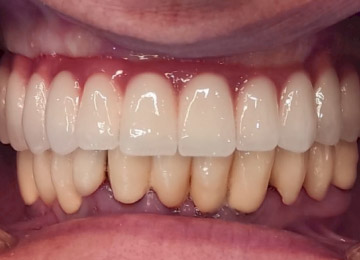

Имплантация зубов: фото «До» и «После»

Фото ДО

Фото ПОСЛЕ

Наведите для просмотра

All-on-4